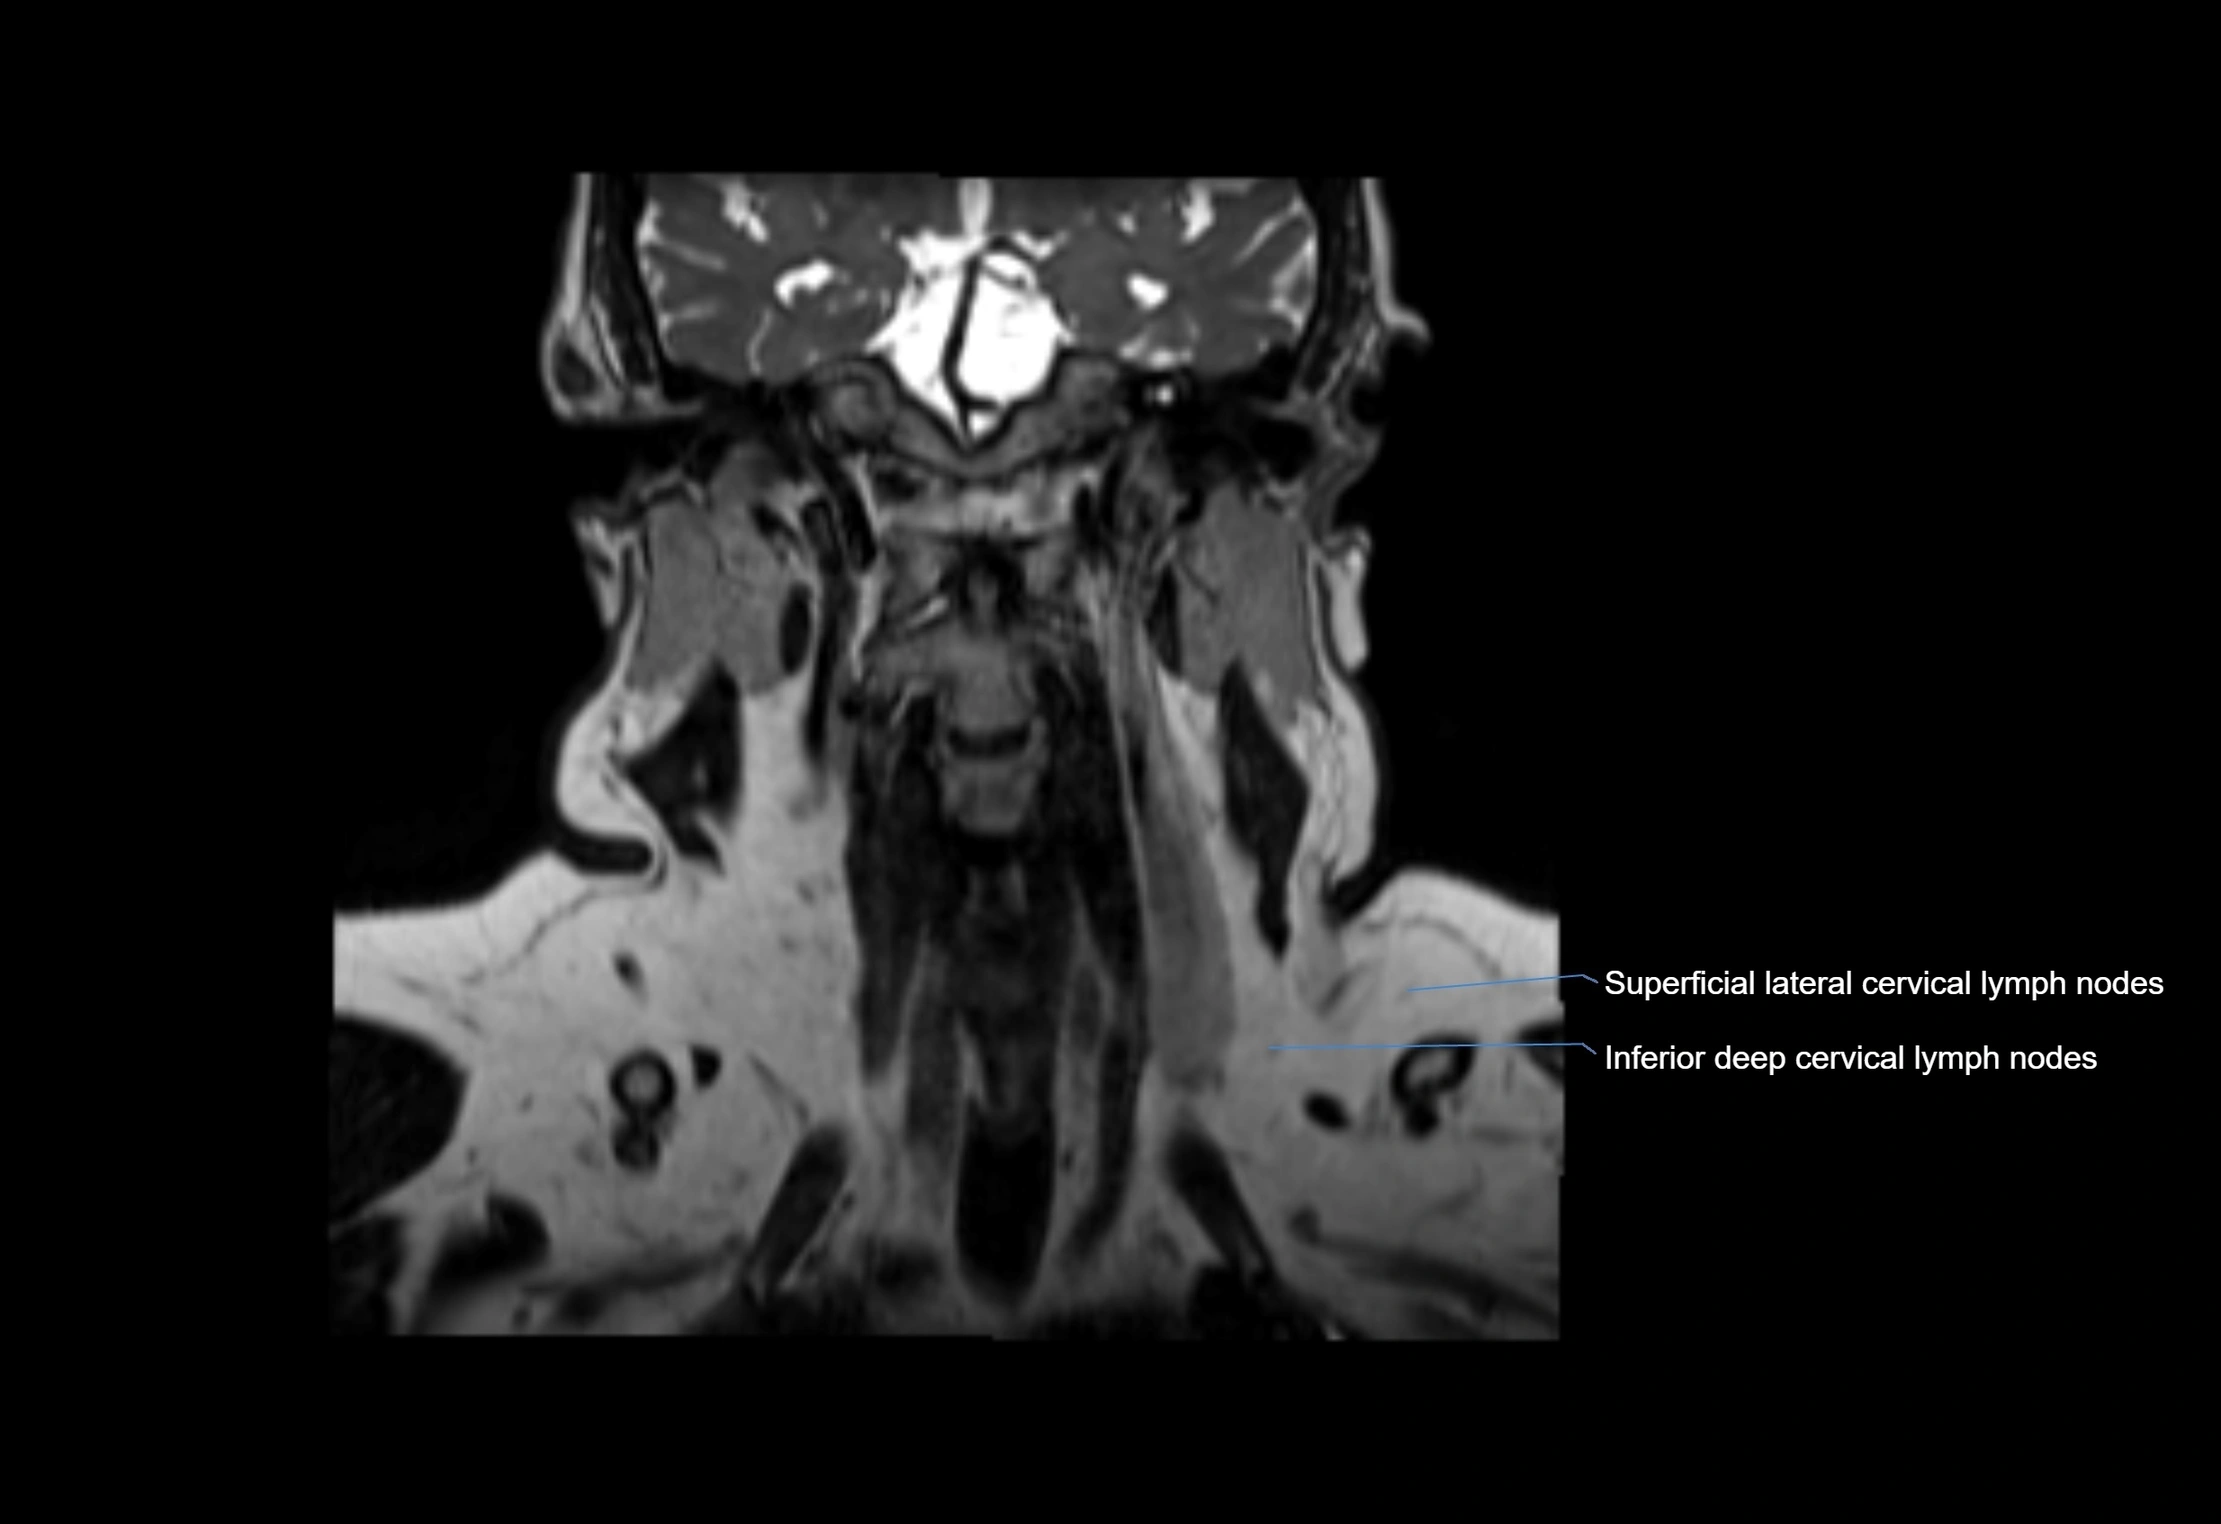

Accessory lymph nodes

Accessory lymph nodes are small, secondary lymph nodes located along the main facial and cervical lymphatic chains, often adjacent to primary lymph nodes, such as preauricular, submandibular, or occipital nodes. They are typically less than 5 mm in diameter, embedded within subcutaneous fat or connective tissue, and may be variable in number and location. These nodes provide additional filtration and immune surveillance for lymph collected from the face, scalp, and neck regions. Accessory lymph nodes are usually non-palpable in healthy individuals but may enlarge in response to infection, inflammation, or metastasis, making them clinically significant.

Location

• Found along primary lymph node chains, including preauricular, submandibular, parotid, and occipital regions

• Embedded in subcutaneous fat or superficial fascia, often lateral or posterior to primary nodes

MRI images

image